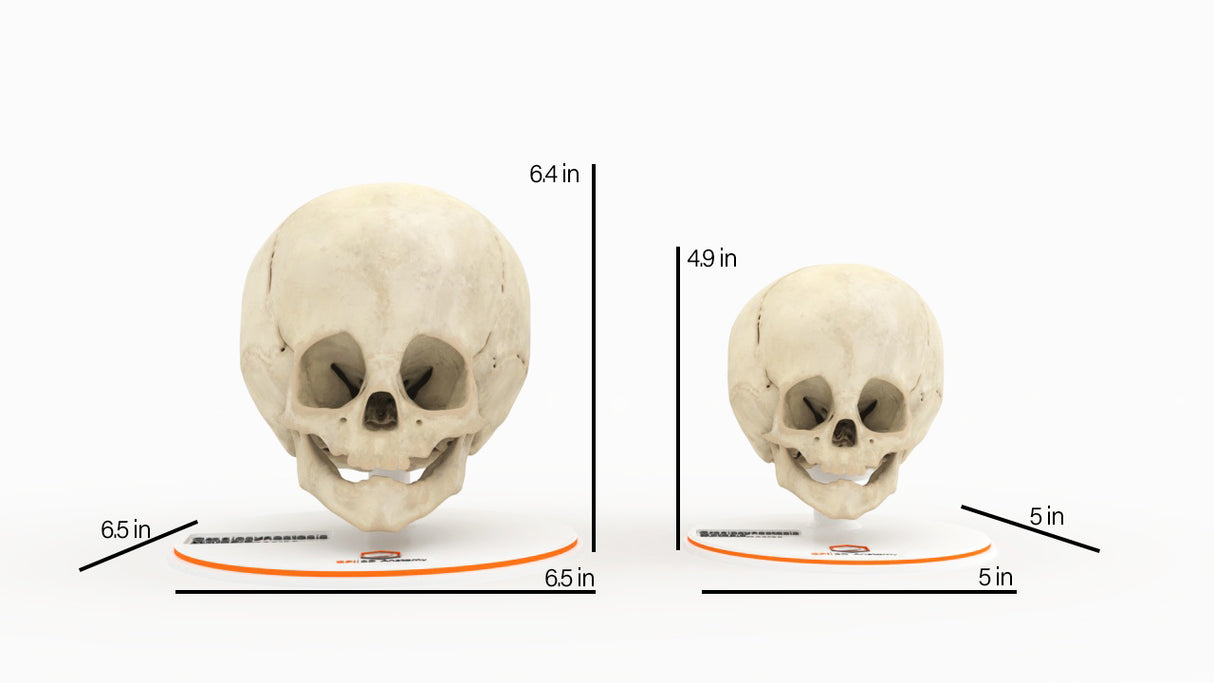

Infant Skull With Craniosynostosis of the Metopic Suture - Male, 8 Months

Infant Skull With Craniosynostosis of the Metopic Suture - Male, 8 Months

Designed using MRI and CT imaging scans and the latest 3D printing technologies, in collaboration with Mayo Clinic.